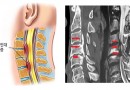

후종인대 골화증

후종인대 골화증(Ossification of Posterior Longitudinal Ligament) (정의 및 원인)척수 신경이 통과하는 척추강의 맨 앞쪽 즉 척추체의 뒷면을 따라 세로로 길게 연결된 인대를 후종인대라고 합니다. 이 후종인대를 따라서 발생되는 비정…

경추부 척추관 협착증

경추부 척추관 협착증(Cervical Spinal Stenosis) (정의)경추(목뼈) 척추관 협착증은 노화로 인해 뼈와 인대가 퇴행하면서 생기는 경우가 많다. 목관절과 주변 인대 및 근육의 퇴행과 더불어 많이 발생하는 퇴행성 척추질환입니다. 디스크를 구성하는 수핵과…